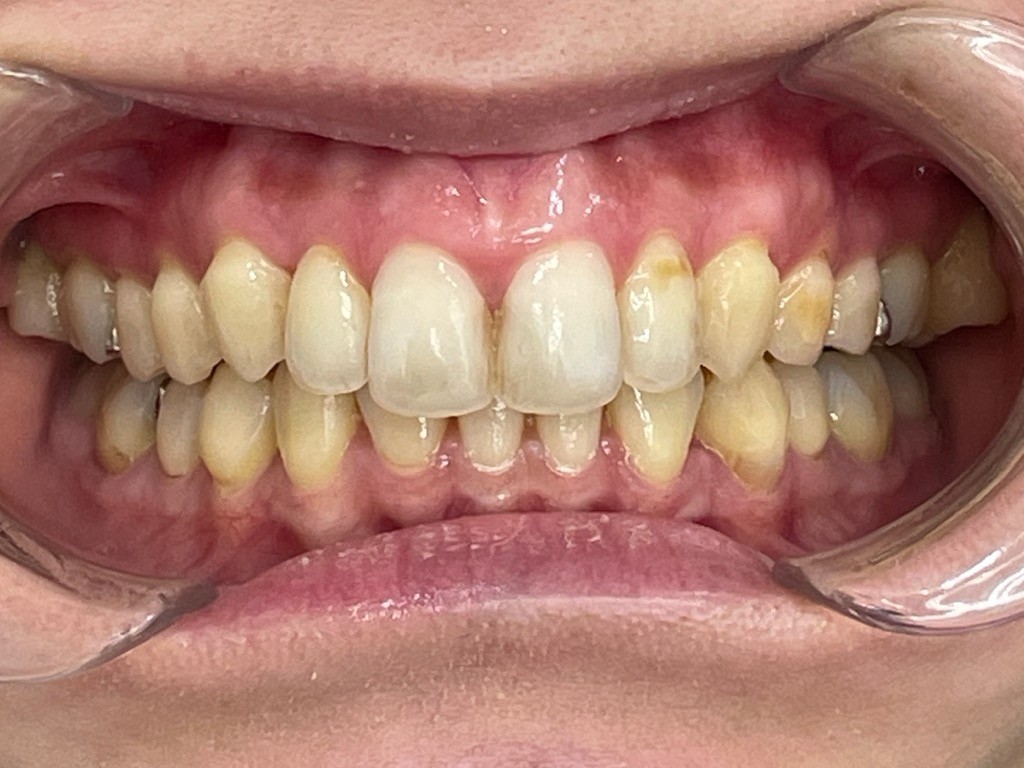

Before

After

矯正の種類 / invisalign GO

年齢・性別 / 30代女性

主訴  /  叢生 かみ合わせ

治療期間 / 17ヶ月

費用 / 簡易検査 5,000円(税別) 精密検査 30,000円(税別)

両額マウスピース 450,000円(税別)  両額リテイナー料 60,000円(税別)

※マウスピース交換時別途調節料3,000円(税別)

副作用 / 口内炎・歯の移動に伴う痛み・知覚過敏 ※数日で収まる場合が多いです

リスク / 後戻り防止の為、夜のみマウスピースで保定を指示